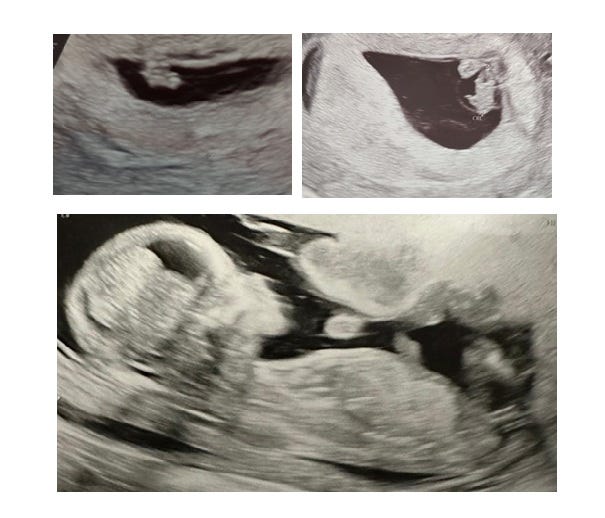

An open letter to the alien living inside me

Third time lucky…

…but the course of IVF never did run smooth.